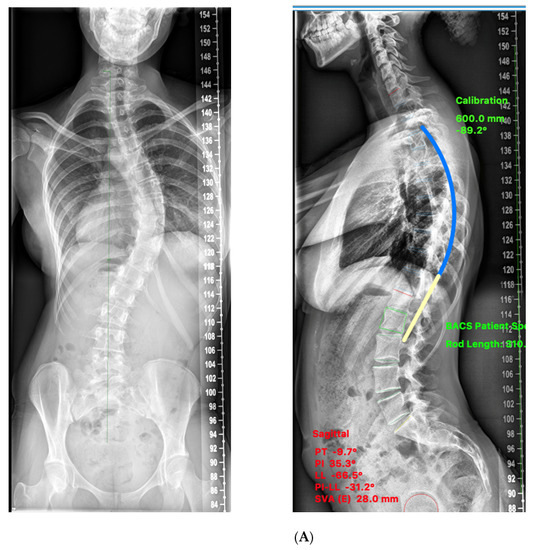

2. Materials and Methods

3.2. Sagittal Plane Correction Parameters

3.3. Comparison of TK Achieved with Templating